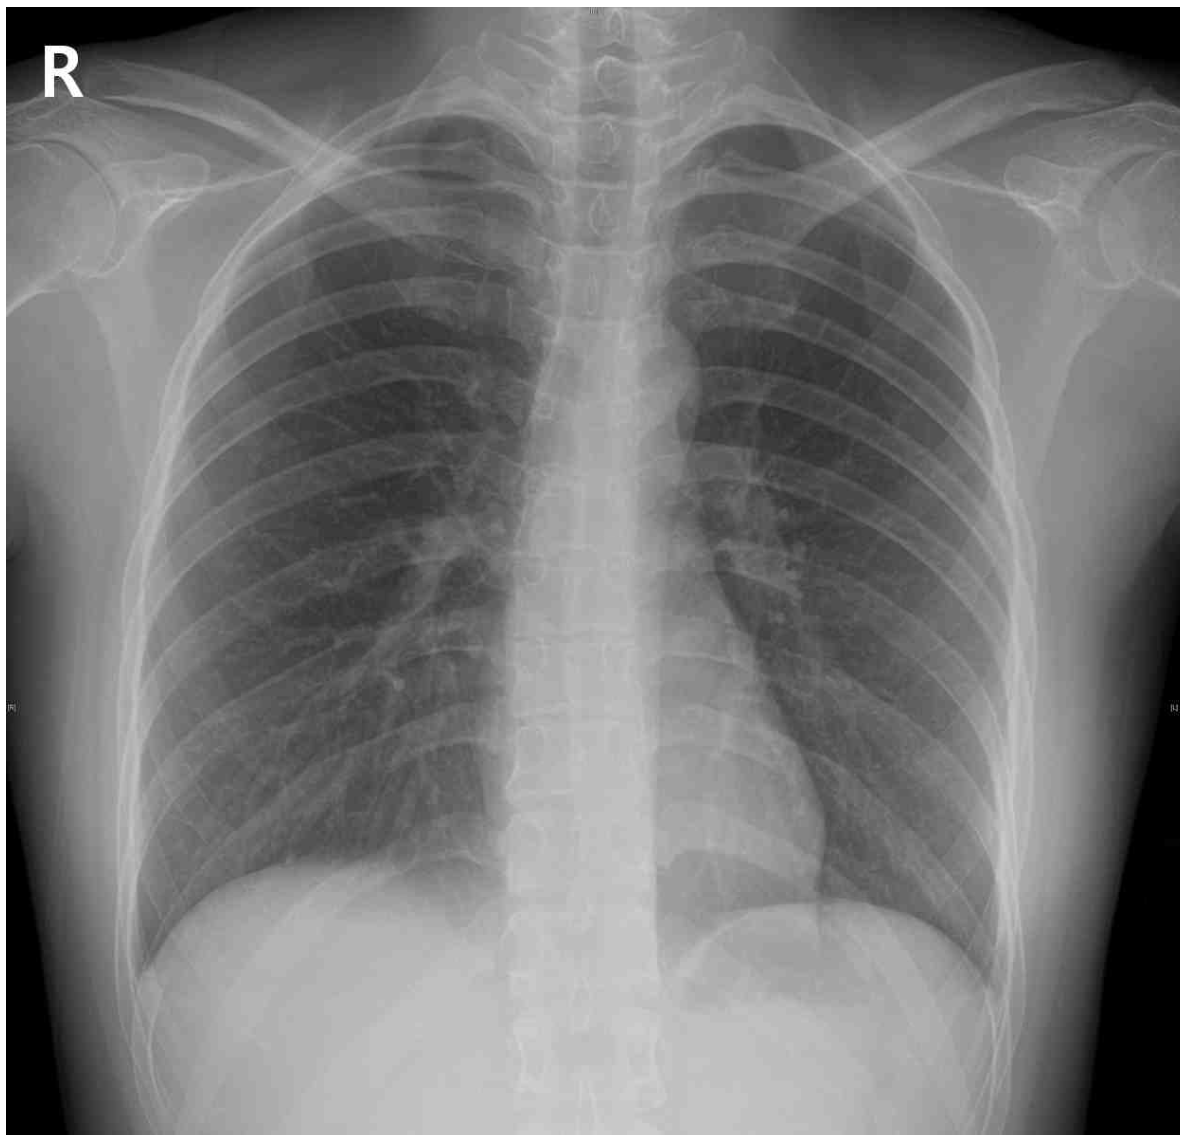

35세 남자가 10일 전부터 기침을 한다며 병원에 왔다. 남자는 초등학교 교사로, 단체여행을 다녀온 후 몸살을 앓았다고 한다. 가래는 기침 끝에 흰색이고 소량으로 나왔다. 비흡연자이다. 혈압 110/60 mmHg, 맥박 80회/분, 호흡 15회/분, 체온 36.8°C이다. 목 안 진찰 소견과 호흡음은 정상이다. 가슴 X선사진이다. 혈액검사 결과는 다음과 같다. 진단은?

CXR: No remarkable findings

기침 및 소량의 가래 외 특이 소견이 관찰되지 않는 환자로 급성 기관지염을 진단할 수 있다.

• V/S상 정상 체온이고 혈액검사상 백혈구 증가와 같이 전신 염증을 시사하는 소견이 확인되지 않으며 가래의 양이 적고 흰색이므로 폐렴, 결핵의 가능성은 낮다.

• 폐결핵: 급성 기침을 나타낼 수 있으나, CXR상 공동이나 결절성 폐침윤 등이 관찰되며 미열, 야간 발한, 체중감소 등의 증상을 호소한다.

• 폐섬유증: 주로 만성적인 호흡곤란을 호소하며 CXR상 reticular opacity가 관찰되므로 기침 및 소량의 가래 외 특이소견이 관찰되지 않는 해당 증례에서는 가능성이 떨어진다.

• 지역사회획득폐렴: 급성 기침을 나타낼 수 있으나 가래의 양이 적고 흰색이며, CXR에서 특이소견이 발견되지 않은 점, 그리고 혈액검사상 백혈구 증가와 같은 염증의 증거를 발견하지 못한 점에서 가능성이 떨어진다.